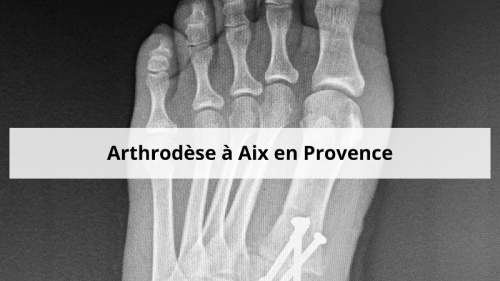

Exemple d'une arthrodèse sur le pied droit

Fixation

Les os sont maintenus solidement avec :

- Vis

- Plaques

- Agrafes

Ces éléments compressent les os du pied droit pour faciliter leur fusion.

Contrôle pendant l’opération

- Radiographie en direct du pied droit

- Vérification de la position et du matériel